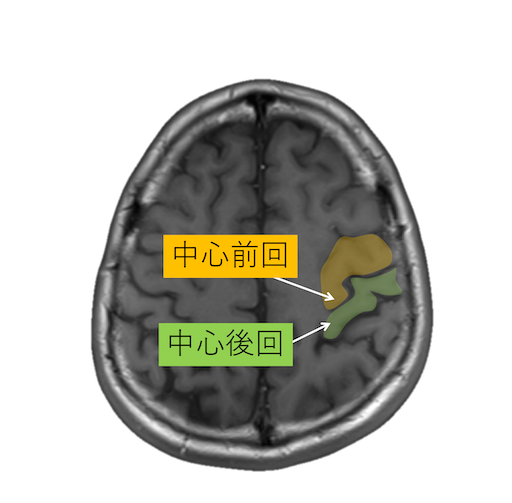

中心溝、中心前溝、中心後溝、中心前回、中心後回のMRI画像における解剖

主に脳梗塞診断などで重要な中心溝、中心前溝、中心後溝、中心前回、中心後回のMRI画像における解剖(CTでも使えます。)をご覧いただけます。

・脳回の前後幅は中心前回が後回より太い。

・中心前回の手指運動野は後方凸を示す(precentralknob sign)